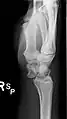

Dislocated lunate

The lunate bone is the most frequently dislocated carpal bone.